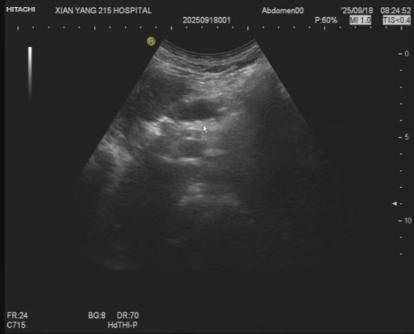

术后

术后的超声复查显示,胰管内结石已被成功击碎,胰管明显通畅,患者状态恢复平稳,未出现胰腺炎急性发作等并发症,现已顺利返回病房。